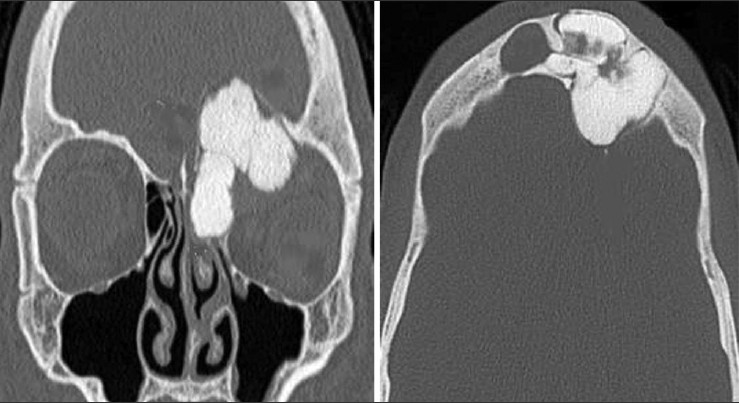

Axial images have a role in the diagnosis of paranasal sinuses problems, but direct coronal scan is better than axial. These results are established by account the number of appearances that showing in coronal view and compared them with those appeared in axial section, where in acute, chronic and fungal sinusitis, the sensitivity of coronal view was (77%, 61% and 61%) respectively compared to axial, which was (22%, 36% and 38%) respectively. In the nasal polyp and granulomatous disease [Figure 2] [Table 1] the efficiency of the coronal view was (62% and 65%), respectively, while in axial was (37% and 34%), respectively. In benign and malignant tumor [Figure 3] and [Figure 4] [Table 2] the efficiency of coronal was 57% and 32% respectively, while in the axial view was (42% and 21%), respectively. | Figure 2: Axial and coronal computed tomography images demonstrate granulomatous disease in a 33-year-old female

| Figure 3: Axial and coronal computed tomography images demonstrate benign osteoma in a 17-year-old man

| Figure 4: Axial and coronal computed tomography images demonstrate frontal sinus osteoma in a 13-year-old man